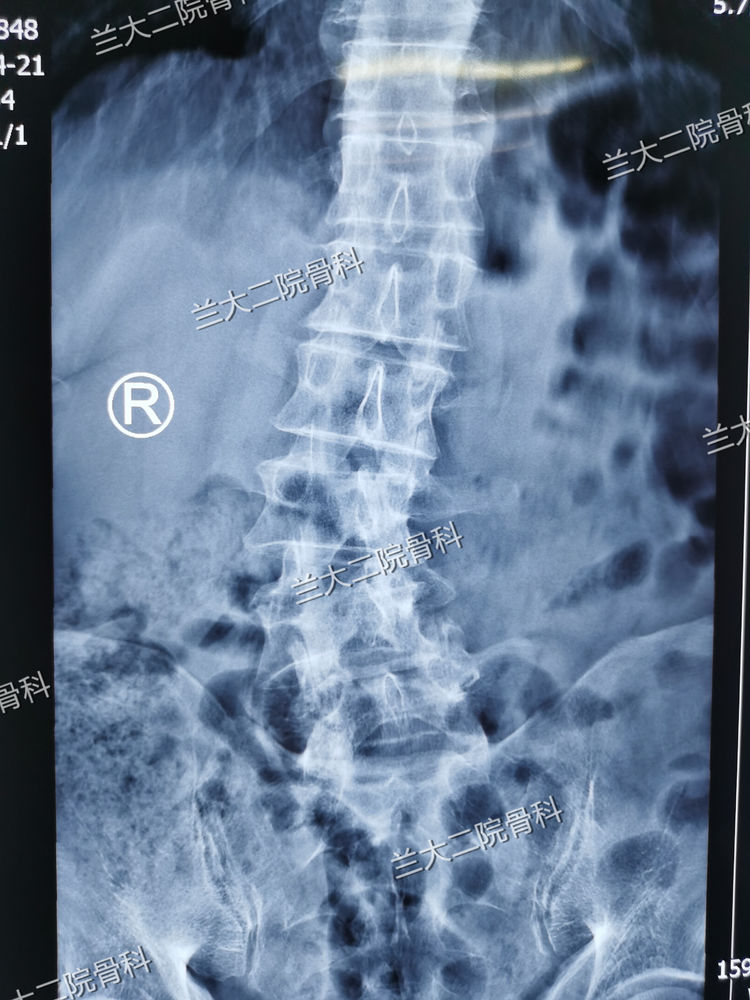

脊柱侧弯旋转畸形

椎管狭窄,脊柱旋转畸形